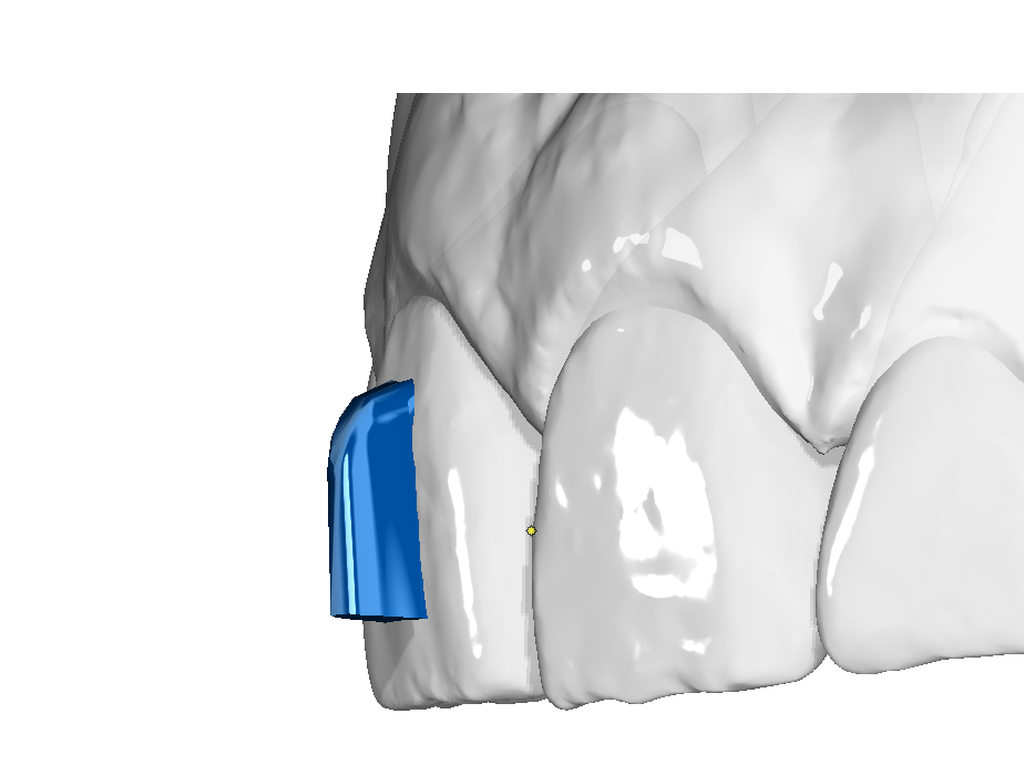

Vertical Attachment Template for Aligner Therapy

The vertical attachment is the workhorse of aligner biomechanics. Its vertical orientation provides the leverage needed for derotation, full bodily movement, and demanding distalization sequences — making it an essential part of any comprehensive aligner case.

✔ Derotation & bodily movement — vertical geometry delivers the control needed for complex 3D tooth movements

✔ Semi-sequential distalization — reliable anchorage for staged posterior movement

✔ Four size options — from 3×2 mm to 6×3.5 mm to match any tooth and indication

✔ Digital O3P template — ready to place directly in OnyxCeph